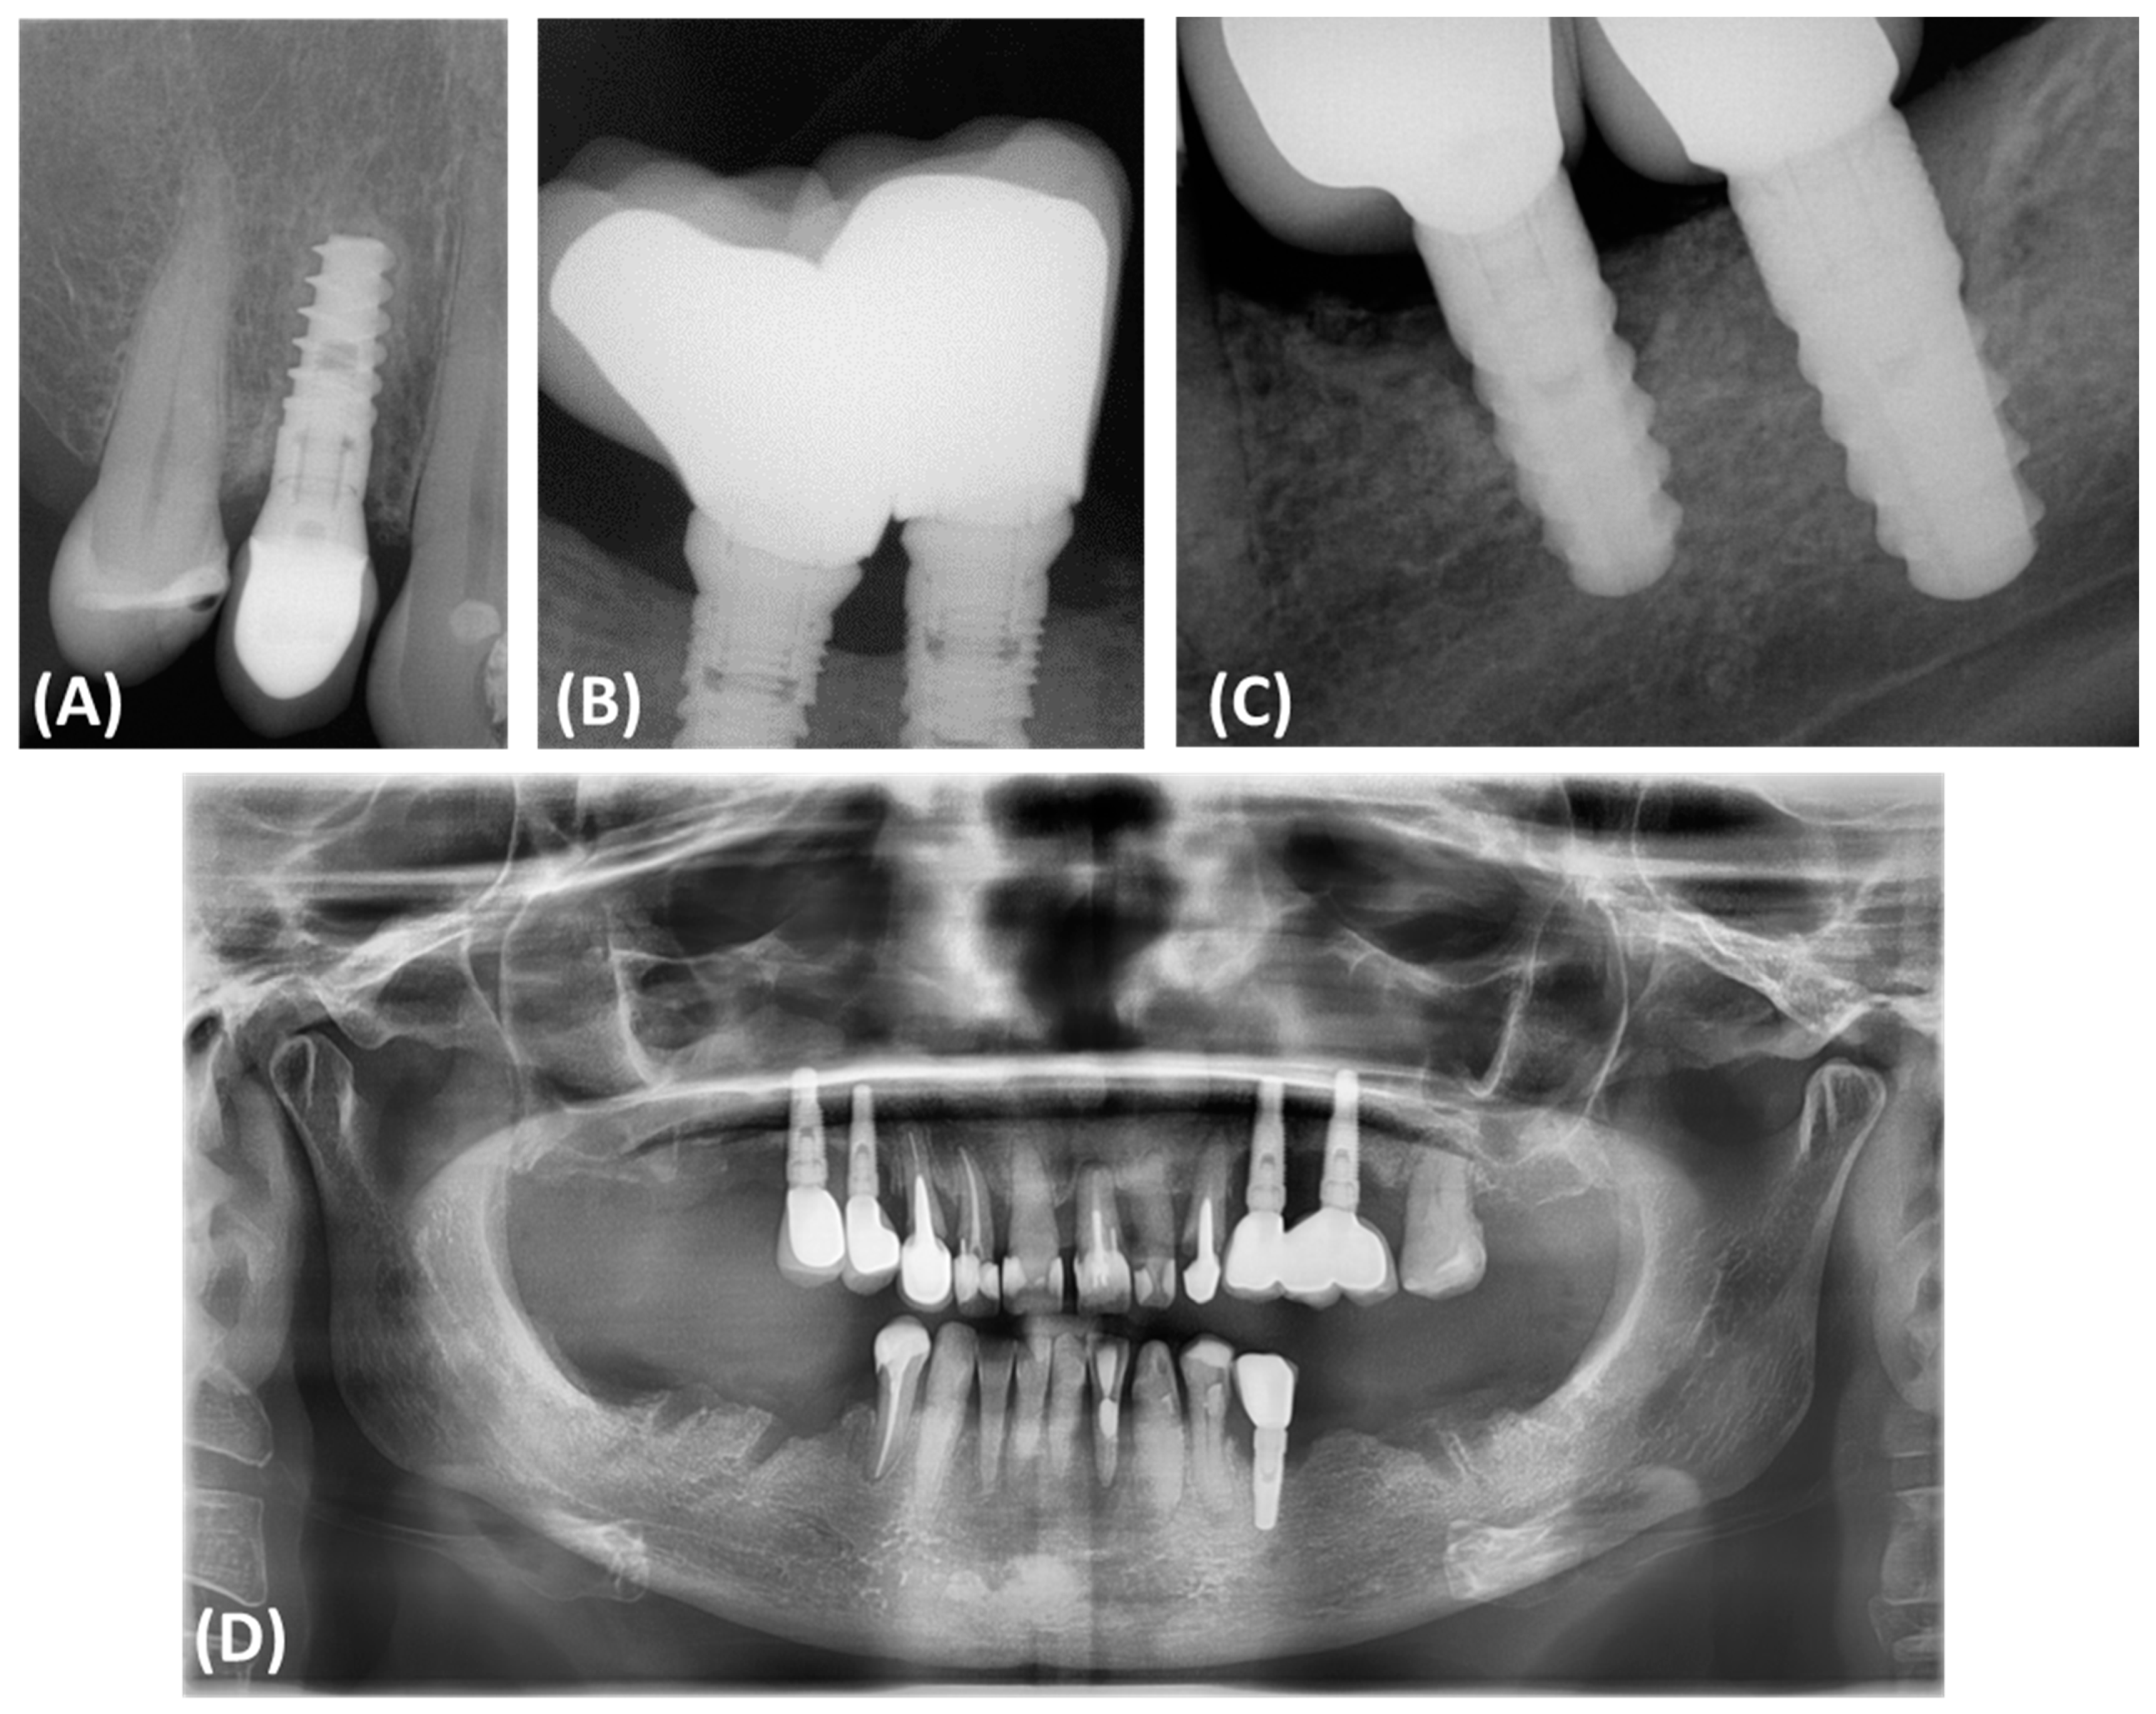

Peri-implantitis often results in bone defects of various morphology and severity, which directly affects the results of reconstruction and complicates treatment decisions. According to Monje and colleagues, bone defects associated with peri-implantitis often have a subosseous component and include significant buccal bone loss. These defects are classified based on morphology and the extent of bone damage, which has an important impact on treatment decisions (Figure 1). Peripheral defects are usually more amenable to regenerative procedures aimed at rebuilding the bone around the implant. However, open defects, especially those with significant cheekbone loss, pose a greater challenge and often require more complex and less predictable treatment strategies [11,12,13,14,15].

Figure 1.

Classification and assessment of the morphology of bone defects associated with peri-implantitis. (A) Radiographic description of bone defects associated with peri-implantitis subosseous defect (Class I); (B) radiographic description of bone defects associated with peri-implantitis horizontal defect (Class II); (C) radiographic description of bone defects associated with peri-implantitis complex defect (Class III); (D) panoramic radiograph of a patient illustrating the presence of Class III bone defects around all implanted dental implants.